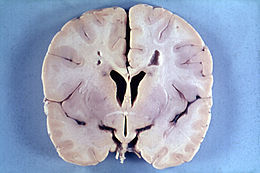

亞歷山大病是一種少見的非家族性白質腦病,典型病例表現為以額葉為主的白質異常和巨腦。腦記憶體在Rosenthal纖維是確診亞歷山大病的組織學前提。臨床特點

目前為最常見類型。症狀通常在出生後1~2年發病,病程多數在2~3年,罕見病例可以存活到十幾歲。典型症狀為發育遲緩、巨腦畸形和癲癇,接下來出現精神運動性遲滯、痙攣和四肢癱。嬰兒通常沒有反應,不會學笑,頭圍漸進性增大,出生後6~18個月頭圍通常超過正常的98%,頭失去控制,偶爾患兒出生時就有巨腦畸形,但也有罕見病例因為顱縫已閉合不出現巨頭。此外部分患兒合併梗阻性腦積水,原因可能為室管膜下出現羅森塔纖維(Rosenthalfibers,RF)導致腦室系統狹窄、閉塞影響腦脊液流通所致。

亞歷山大病是一種遺傳性疾病,影響中樞神經系統(中腦和小腦)。它是一種與膠質纖維酸性蛋白(GFAP)相對應的染色體17q21段的基因突變。這種病是一種隱性遺傳代謝性疾病,所以若孩子的父母帶有這個基因突變,他們的子女會有一半機會遺傳有這種病。亞歷山大症屬於腦白質失養症(Leukodystrophy)的一種類型:“腦白質失養症”又名“腦白質營養不良”,但這病症跟營養不良無關,而是指一組白質脫髓鞘性病變,會影響髓鞘發育或生長。亞歷山大症患者會由於脂肪酸代謝障礙,令極長鏈脂肪酸在腦白質異常積累,使腦白質被破壞,並形成一種纖維狀的嗜酸性粒細胞沉積,稱為羅森塔爾纖維(Rosenthalfiber)。這一種羅森塔爾纖維並不存在於健全人士,只會在某些特定的病症,例如一些癌症的患者身上出現,分別只在於羅森塔爾纖維在亞歷山大症患者身上出現的位置與其他病變患者並不相同。

根據亞歷山大症患者的計算機斷層掃描(CT)顯示:

患者的腦白質密度較低;

腦額葉占主導性;

+/-側腦室擴張